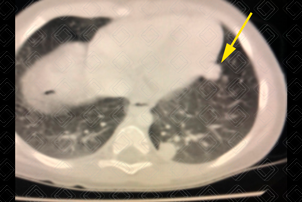

Texto alternativo para a imagem Figura 2. Créditos: Dra. Elazir Mota - Rio de Janeiro/RJ

Descrição da figura 2: Tomografia computadorizada de tórax de controle (realizada 3 meses após o primeiro exame). Houve surgimento de um segundo nódulo pulmonar, também no lobo inferior esquerdo (seta amarela).